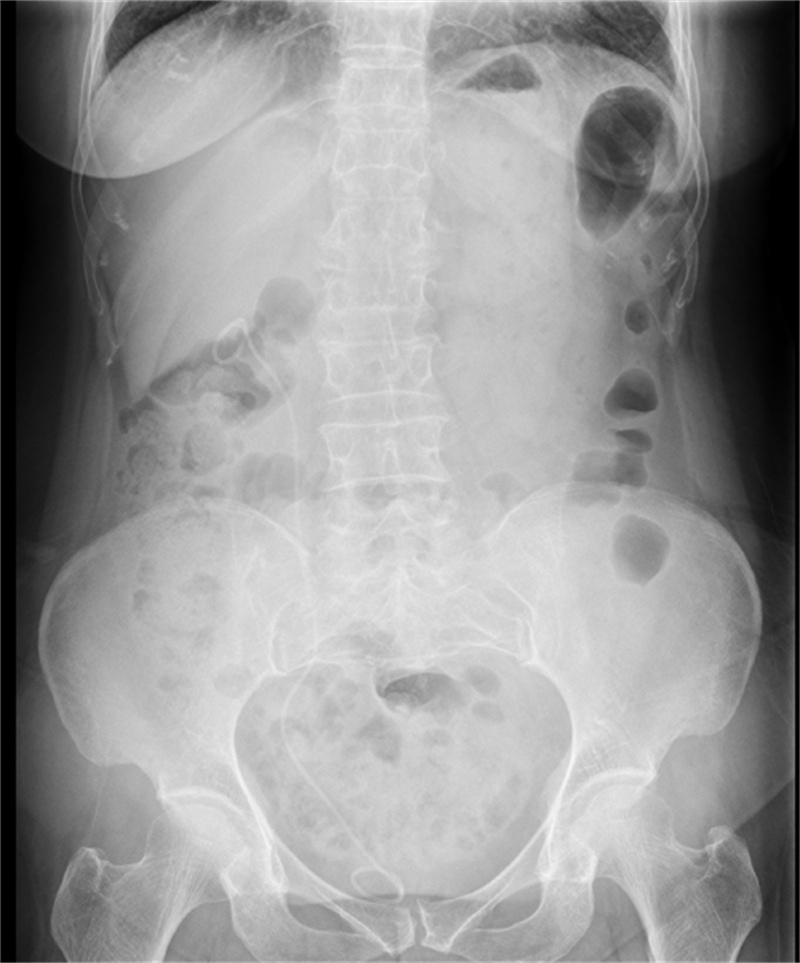

术后X线显示结石被完全清理干净

术后第三天,王女士便痊愈出院,出院之际,对科室的医护团队连连称赞,感激不已。